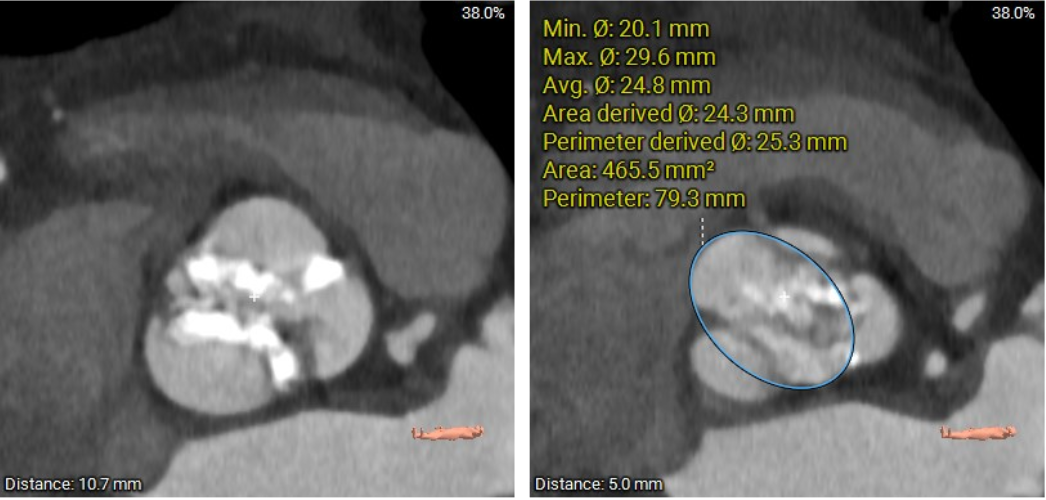

瓣环及左室流出道:

主动脉瓣的开口面积的估计(在瓣环平面5mm 以上测量):